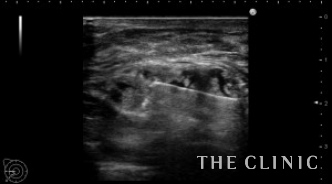

除去した壊死脂肪と術後10日目のエコーです。

しこりは完全に消失しています。